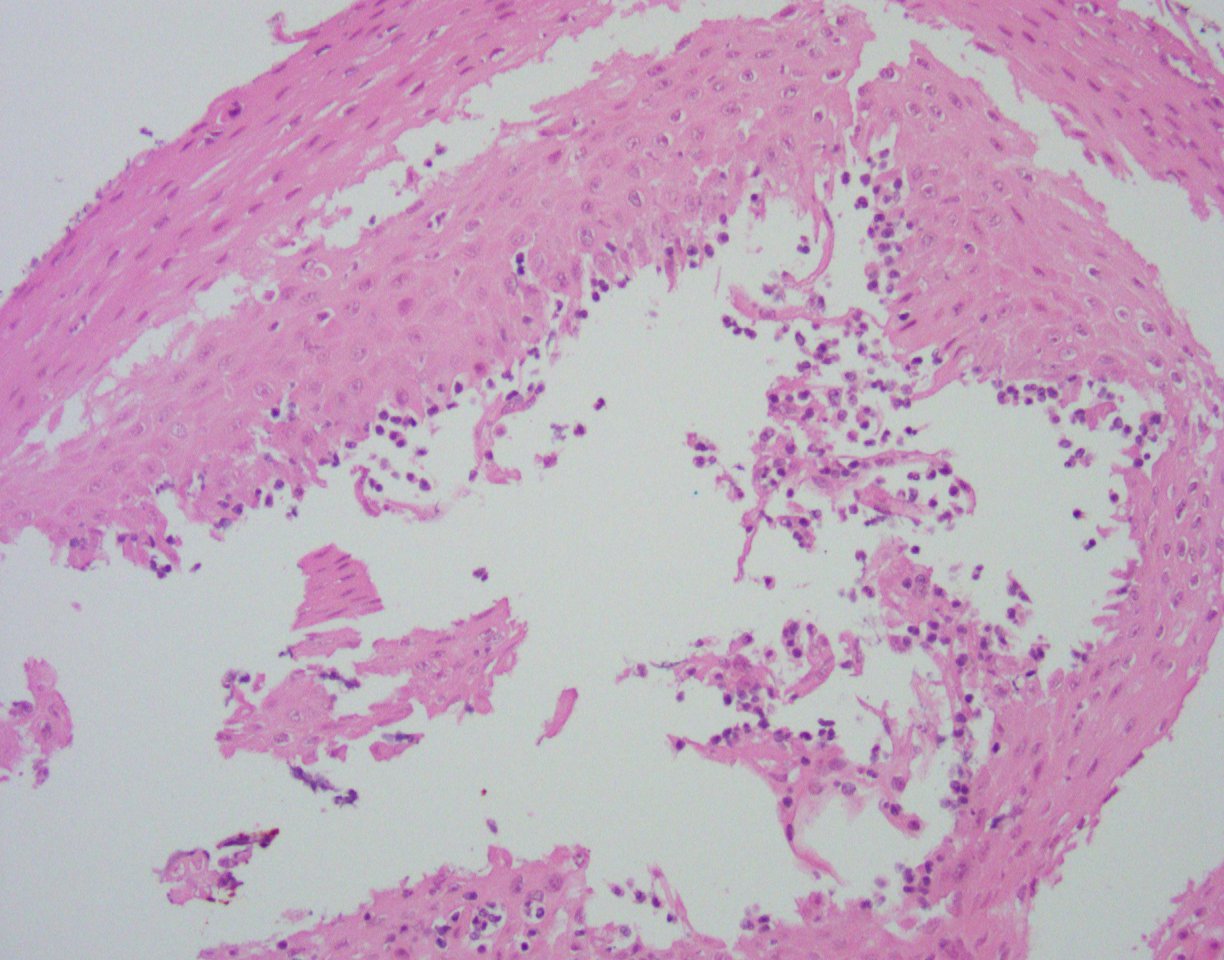

Histologically, the esophageal mucosa demonstrates hypertrophied squamous epithelium with a superficial zone of eosinophilic epithelium (Figures 1, 2). The superficial epithelium exhibits necrosis with faded or ‘ghost-like’ nuclei (Figure 2). A band of neutrophilic inflammation can be seen in some areas separating the two epithelial layers (Figure 3). Some of the tissue fragments in this biopsy specimen consist solely of the superficial necrotic material and neutrophilic junctional layer (Figure 4). GMS stain is negative for fungal organisms (Figure 5).